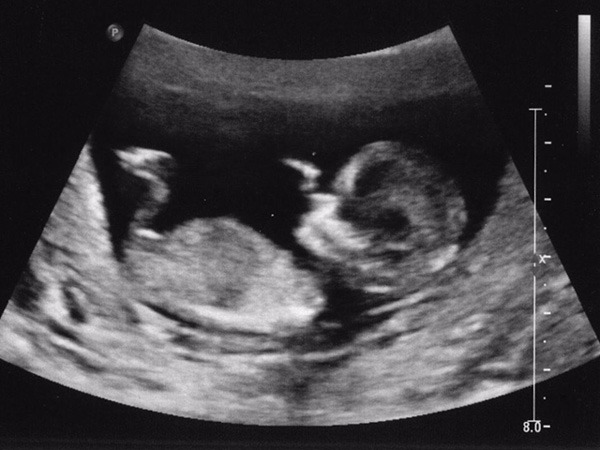

Thai nhi 12 tuần tuổi là thời điểm thích hợp để mẹ thực hiện siêu âm và kiểm tra một số chỉ số sức khỏe của con. Tại thời điểm này, thai nhi đã phát triển cơ bản đầy đủ về các chức năng của mọi hệ cơ quan, bắt đầu hình thành các giác quan, hệ cơ và các bộ phận của cơ thể. Hình ảnh thai 12 tuần cũng có thể giúp mẹ phát hiện những thay đổi bất thường của thai nhi nếu có để phòng ngừa dị tật bẩm sinh.

Bên cạnh việc siêu âm để theo dõi quá trình phát triển của bé, nhiều gia đình còn thực hiện siêu âm để giải đáp thắc mắc 12 tuần biết trai hay gái chưa. Nhờ sự phát triển trong cấu trúc cơ quan sinh dục với những chuyển biến rõ rệt nên hình ảnh siêu âm bé trai 12 tuần hay bé gái có thể giúp bác sĩ xác định giới tính thai nhi nhưng chưa thể chính xác hoàn toàn.